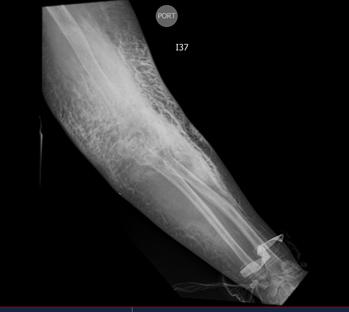

Las extravasaciones de medio de contraste se dividen en tres categorías según su gravedad. La extravasación leve, representativa en el 97,4% de los casos, se manifiesta con síntomas leves como dolor, edema o eritema, y generalmente se resuelve por sí sola. La moderada, que ocurre en un 2,2% de los pacientes y presenta síntomas más intensos como edema marcado, eritema y dolor persistente, pudiendo formarse vesículas que suelen desaparecer en dos semanas. La extravasación severa (Figura 1), presente en aproximadamente el 0,4% de los casos, exhibe síntomas graves como dolor intenso, edema severo y limitación en la movilidad, pudiendo desarrollar el síndrome compartimental y persistir por más de dos semanas (12).

Tac de brazo izquierdo, paciente quien fue canalizado en región braquial, se evidencia en el área colección de medio de contraste. Figura 1.